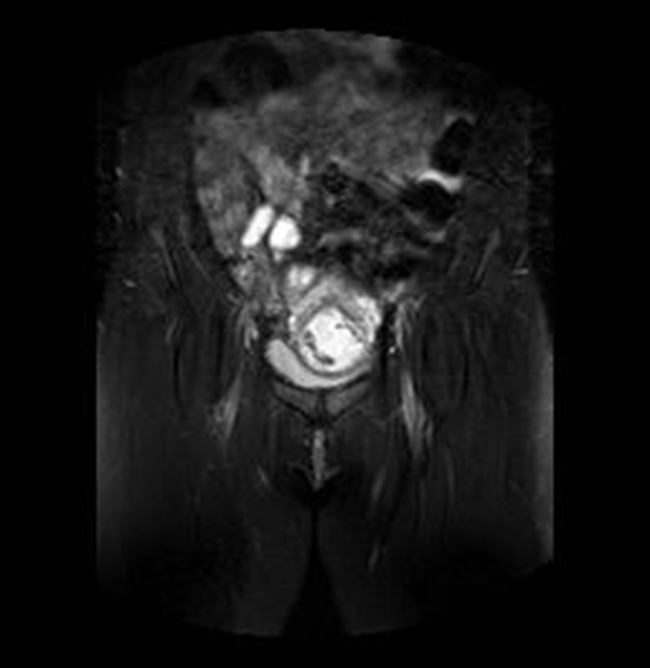

Se realizó una RNM (Philips 1.5 Tesla) que permitió confirmar el diagnóstico de EEC (figuras 5 a 8).

Figura 7A Imágenes de RMN potenciadas en T2 con supresión de la grasa. A) Plano axial y B) Plano coronal, donde se identifica el saco gestacional como una estructura quística con tejido fetoplacentario en su interior y localizado en el canal cervical

Figura 7B Imágenes de RMN potenciadas en T2 con supresión de la grasa. A) Plano axial y B) Plano coronal, donde se identifica el saco gestacional como una estructura quística con tejido fetoplacentario en su interior y localizado en el canal cervical